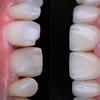

Zirkonyum uygulamalar

Porselen uygulamaları

Laminate veneer